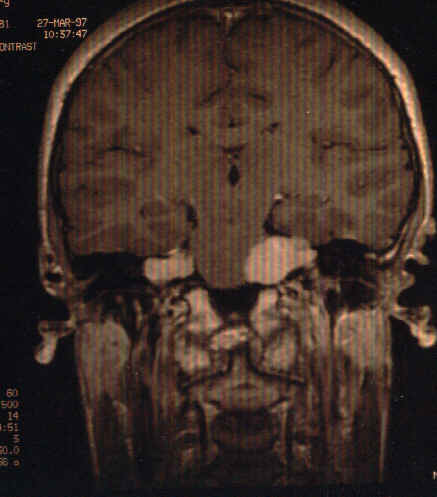

The MRI scan (Fig. 1) which is T2 weighted (as the vitreous and the cerebrospinal fluid are all white) shows bilateral solid lesions at the junction of the cerebellum and the pons. The most likely diagnosis is bilateral acoustic neuroma. The lesions are further delineated with the coronal and sagittal views in Fig.2 and Fig. 3.